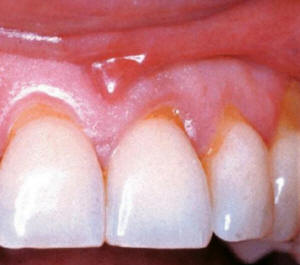

- Explorar la encía:

Gingivitis o enfermedad periodontal leve, moderada y severa contraindica

el tratamiento. Dado que el sangrado y la exposición de la

dentina y cemento malogran los tratamientos blanqueadores. Las

encías retraídas dejan espacios interdentales oscuros, el

cemento dental decolorado no se blanquea. A veces junto con el

tratamiento blanqueador es necesario

confeccionar carillas para eliminar los defectos de color y

forma.

Retracción

gingival |